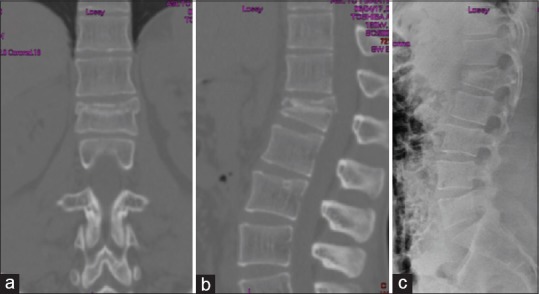

Figure 2.

CT scan of a 18-years-old male with type A3 L1 vertebral fracture in coronal (a) and sagittal plane (b). X-ray of the same fracture in lateral view (c)